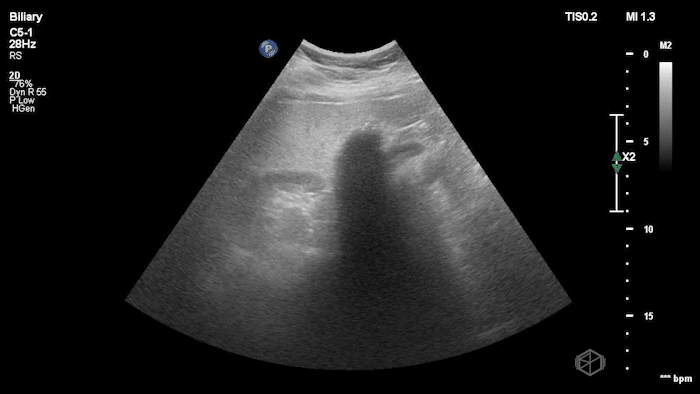

08 - What are the 6 signs of cholecystitis and what signs are visible here?

6 signs of cholecystitis — aGBW thickening >4mm, gallbladder wall edema, stone-in-neck (SIN) sign, pericholecystic fluid, hydropic gallbladder 10cm x 5cm, sonographic Murphy’s

Signs visible on this scan — SIN, hydropic gallbladder, gallbladder wall thickening